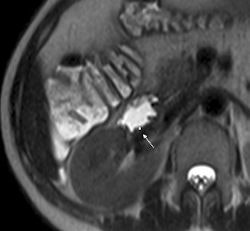

| 1.5-tesla MR images show a portion of the duodenum wall in a patient with untreated celiac disease (above), a patient with treated celiac disease (below), and a healthy patient (bottom). The images show no significant differences in duodenal wall thickness (arrow). |

Their analysis found that a mean maximum enhancement of the duodenal wall was 229.1 ± 46.4 in untreated patients with celiac disease, 109.8 ± 27.8 in treated patients with celiac disease, and 94.7 ± 17.9 in control subjects.

"This MR parameter was significantly higher in patients with untreated celiac disease than in patients with treated celiac disease and control subjects," the authors wrote, while maximum enhancement did not significantly differ between the patients with treated celiac disease and controls.

The researchers also found that duodenal wall thickness did not significantly differ between patients with celiac disease who were not treated for the condition, patients with celiac disease who were treated, and healthy control subjects.